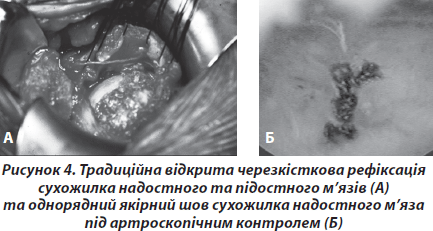

Сукупність даних клінічного, ультразвукового методів та магнітно-резонансної томографії, що підтверджувала наявність у хворого ознак розриву сухожилків РМП, вважалась нами показанням до оперативного втручання. Оперативне втручання проводили у відкритий спосіб та під артроскопічним контролем із застосуванням техніки однорядного шва до металевих або біодеградуючих якорів [5] (рис. 4).